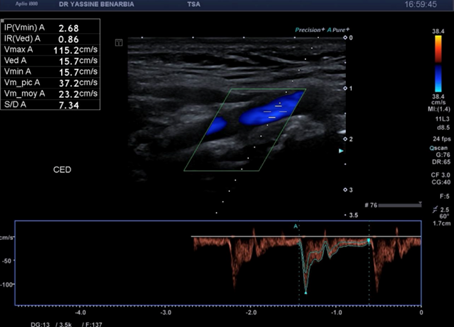

Cette dissection s'étend à la carotide commune droite proximale. Le Doppler pulsé dans le vrai chenal montre un spectre triphasique conservé avec une vélocité maximale de 108,0 cm/s (normale) et un index de résistivité de 0,84 confirmant l'absence de retentissement hémodynamique. L'artère sous-clavière droite et l’artère vertébrale restent perméables avec des flux normaux au doppler.

Les signes retrouvés à l'échographie-Doppler sont : flap intimal mobile visible en mode B séparant vrai et faux chenal, double lumière artérielle en coupe transversale et longitudinale, flux différenciés au Doppler couleur (vélocités élevées dans le vrai chenal, flux plus lent dans le faux chenal), et spectre Doppler pulsé conservé dans le vrai chenal (triphasique ou biphasique).

Les critères de stabilité à surveiller sont : taille du faux chenal inchangée, flux conservé dans le vrai chenal avec vélocimétrie normale (Vmax < 125 cm/s), absence d'extension de la dissection, absence de thrombose progressive, et absence de dilatation anévrysmale.